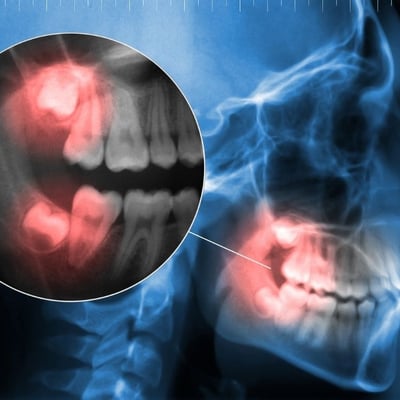

Cirurgias de sisos, implantes dentários, biopsias, diagnósticos de patologias orais